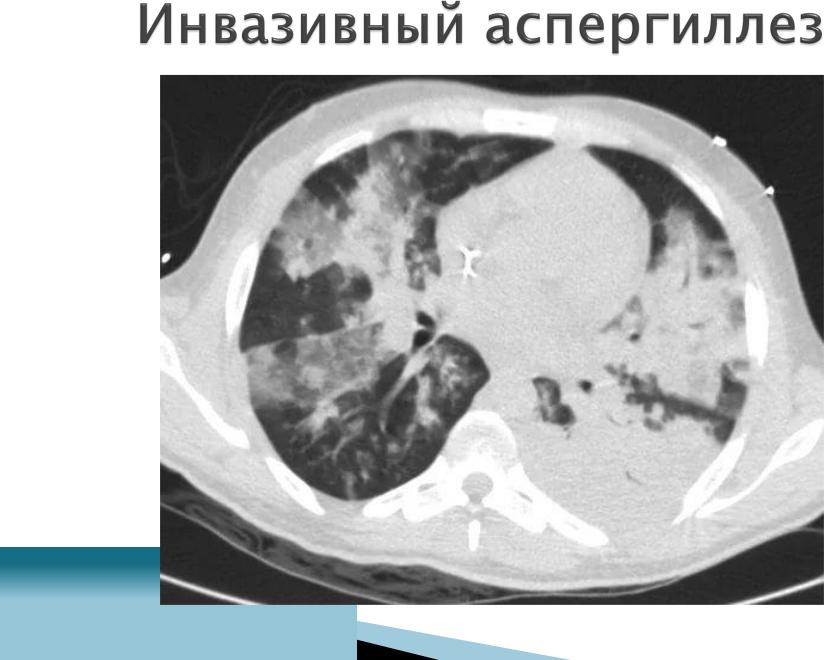

Диагностика -КТВР легких

-МРТ ГМ

-ФБС, БАЛ, биопсия очагов

-определение АГ гриба (галактоманнана)

всыворотке, БАЛ

-микроскопия, посев мокроты, БАЛ

Лечение: препарат выбора -вориконазол в/в 6 мг/кг каждые 12ч, затем внутрь 400 мг/сут